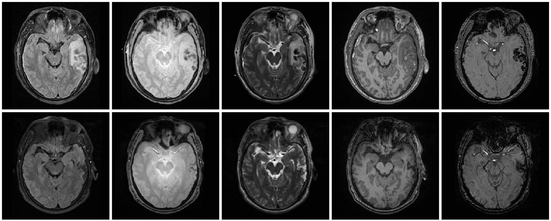

Multimodal MRI data of TBI patient.

We are working on an extension of the "atlas-based classification" method ABC for TBI datasets with the clinical goal to efficiently segment healthy brain tissue and cerebral lesions. A main goal will be the automated segmentation of healthy brain tissue and user-assisted segmentation of various cerebral lesion types (hematoma, subarachnoid hemorrhage, contusion and DAI, perifocal (regional) to diffuse (generalized) edema, hemorrhagic diffuse axonal injury (DAI)and more. A strong emphasis will be on the joint analysis of multiple imaging modalities (T1 pre- and T1 postcontrast, T2 (TSE), FLAIR, GRE, SWI, Perfusion, and DTI/DWI) for improved detection and quantitative characterization of lesion types.